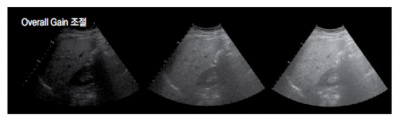

기본적인 영상 조절 ④ : 전체 게인(Overall gain) 조절

깊이에 관계없이 반사되어 돌아오는 모든 에코를 동일하게 증폭시키는 것을 전체 게인이라 하며 통상적으로‘ 게인’이라고 말한다. 전체 게인을 너무 높이면 실제 장기에서 돌아오는 초음파 에코뿐만 아니라 산란되어 오는 에코도 같이 증가하기 때문에 병변의 선명도가 떨어진다. 반대로 전체 게인을 너무 낮추면 산란 에코는 제거할 수 있지만, 실제 필요한 에코까지 제거되므로 정확한 정보를 얻을 수 없다.